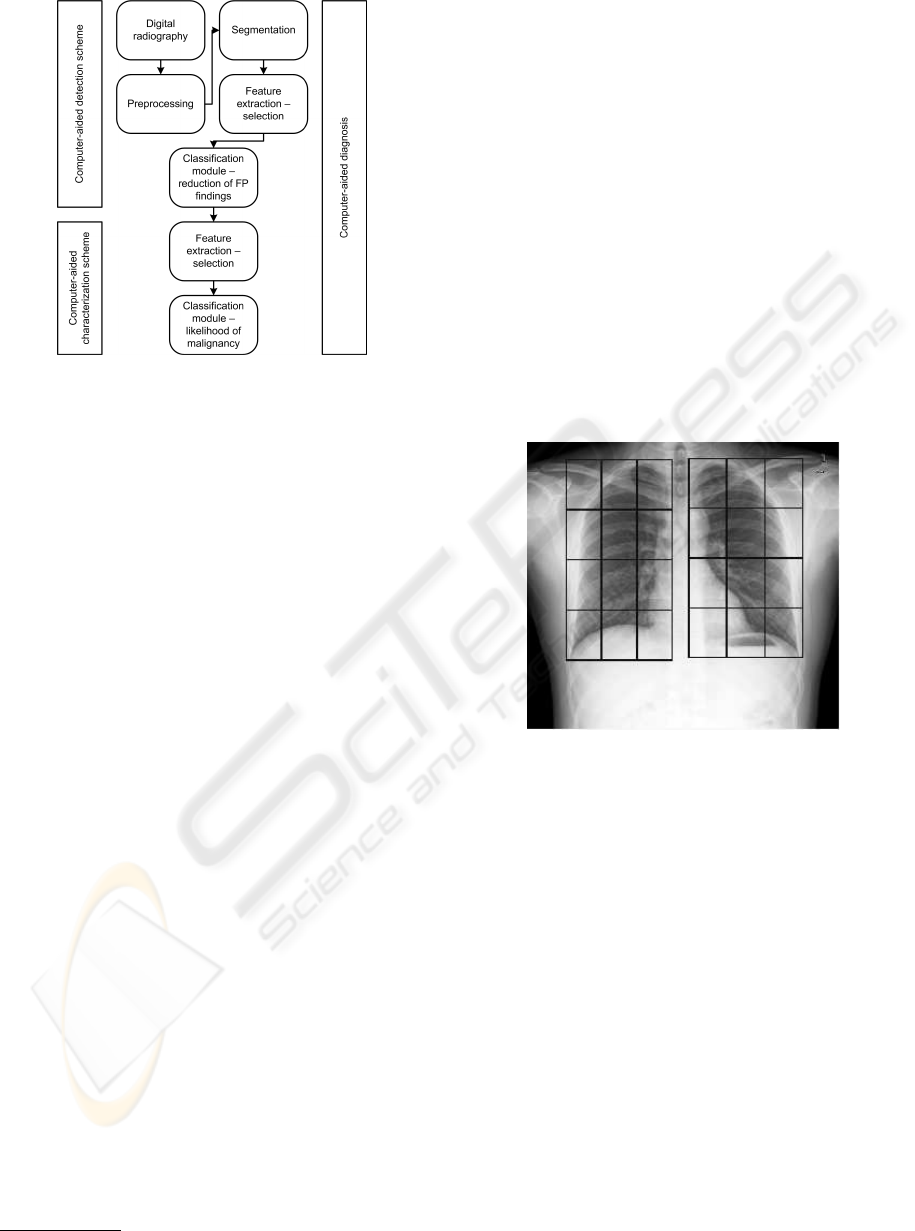

Figure 7: Accuracy obtained with different classifiers with

and without using discrimination matrix.